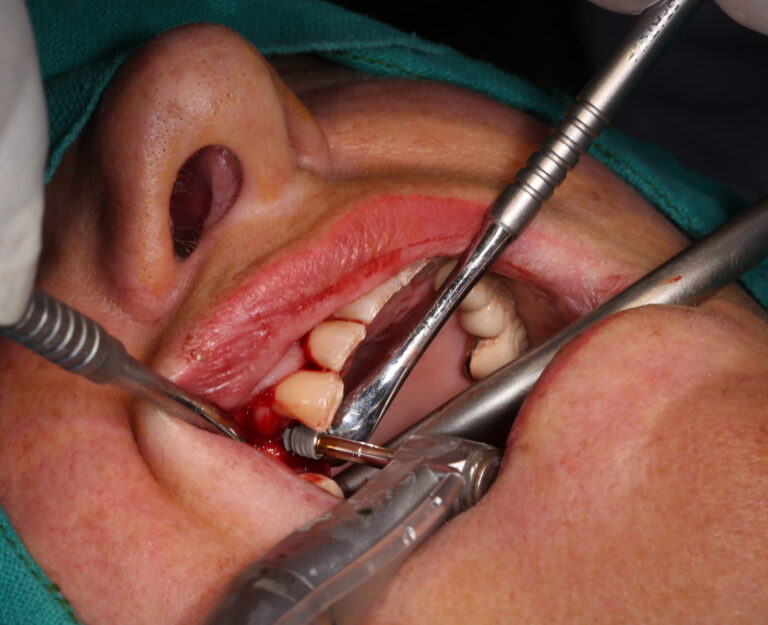

A middle aged foreign female patient booked an appointment at our Big Smile Dental Clinic & Prosthodontic Center, Kathmandu, Nepal. Upon examination she had missing upper right 1st premolar tooth. After thorough examination and counseling, we planned for dental implant.

Dental implant was placed on planned position successfully. Procedure was done by experienced specialist and treatment was painless and uneventful. Patient was comfortable and happy after successful placement of dental implant. Next appointment has been appointed after 4 to 6 months for prosthesis procedure.